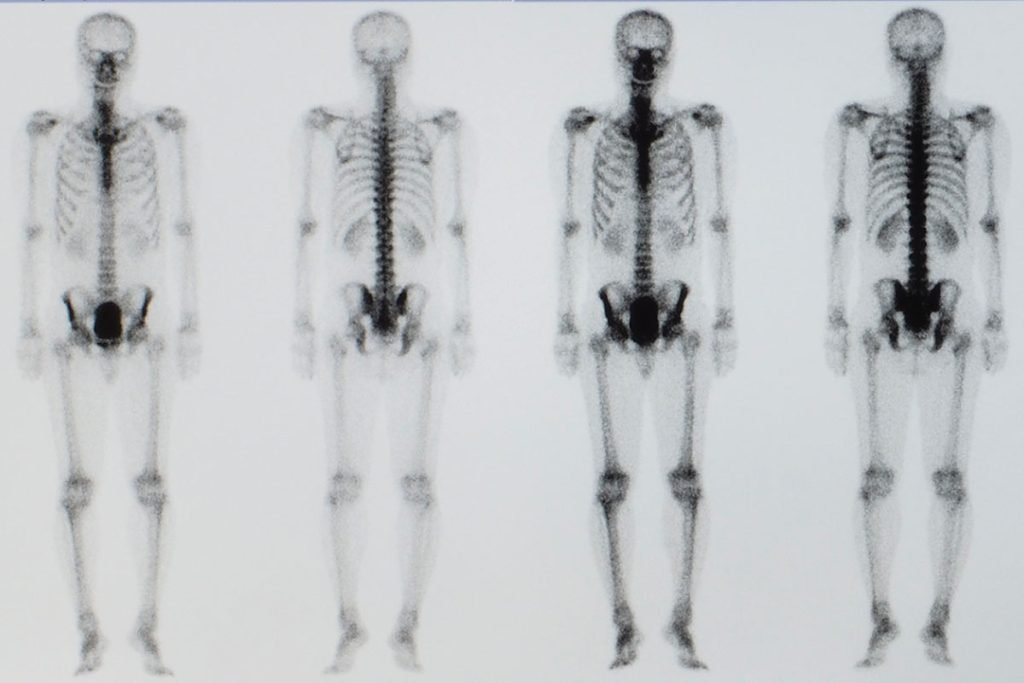

Scintigrafia ossea

Si tratta dell’indagine di scelta volta ad indagare l’eventuale presenza di lesione secondarie a livello osseo, sito preferenziale di metastatizzazione del tumore prostatico.

Da quanto si evince dalla letteratura, il rischio di metastasi a livello osseo sussiste in particolare in caso di PSA > 20 ng/mL o di malattia con Gleason Score > 8. Nelle malattie a basso rischio, tale indagine sarebbe pertanto da evitare. L’accurata selezione dei pazienti permette di ridurre il tasso di falsi negativi all’1%, portando la sensibilità vicina al 100%.

In caso di riscontro di lesioni di non univoca interpretazione possono essere eseguiti ulteriori approfondimenti mirati quali radiografie, RM o TC.